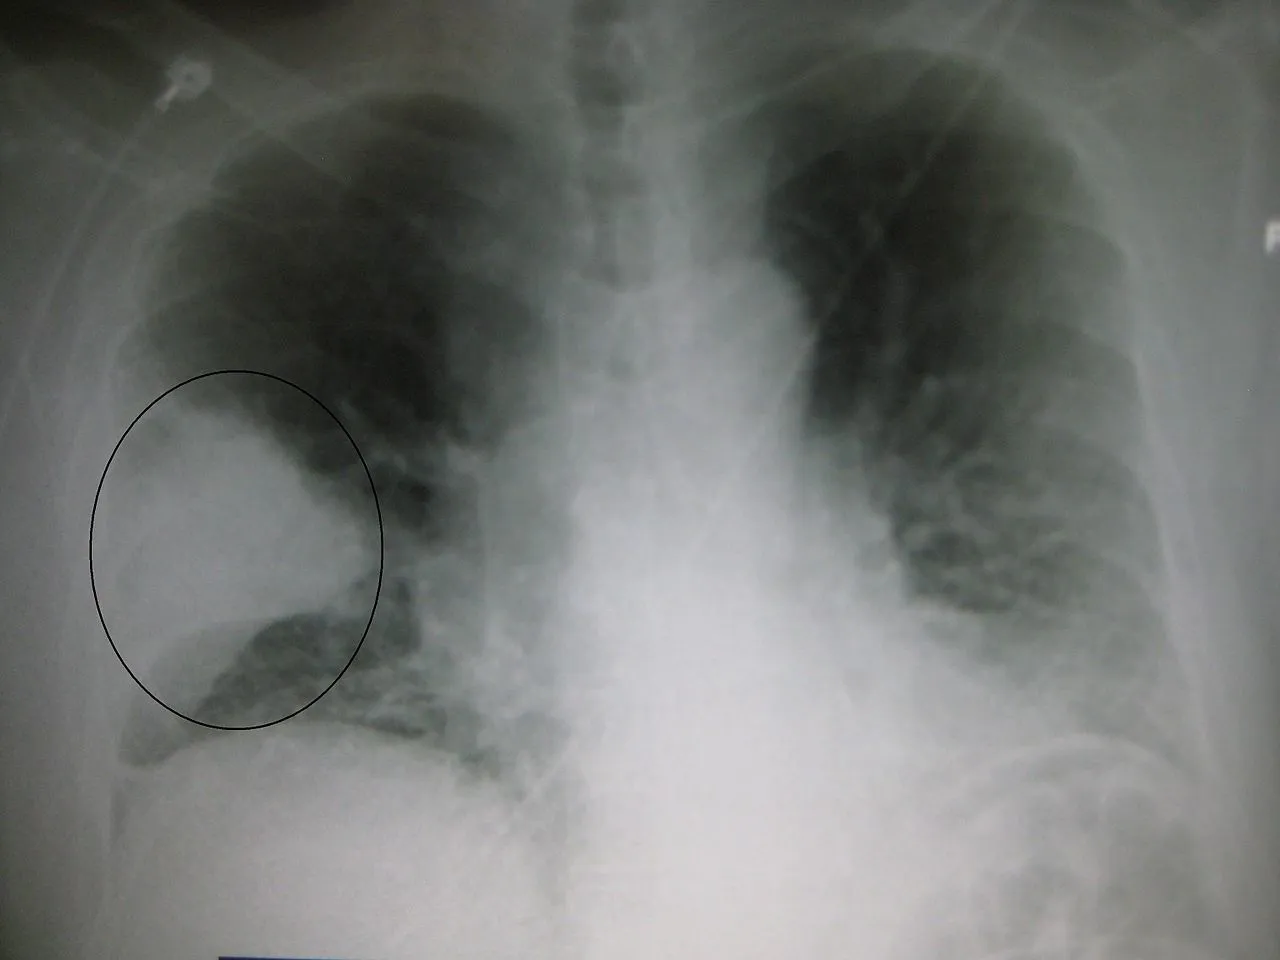

Une pneumonie sévère du lobe du poumon droit :